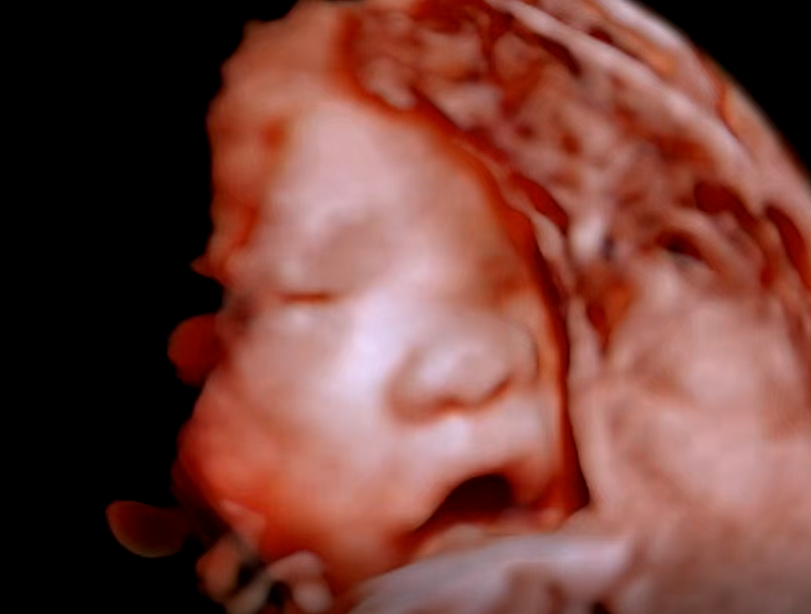

주수가 더 지날수록 아기 얼굴이 잘 안보인다고 하여 25주에 받게된 5D 정밀초음파. 호띵이의 얼굴을 입체적으로 볼 수 있다고하여 설레는 마음으로 예약한 시간에 맞게 초음파실에 들어가게 되었다.

호띵이의 자세가 매순간 바뀜에 따라 얼굴보기가 어려웠다. 그리고 얼굴에 계속 손을 가져다대서 온전하게 얼굴을 볼 수 있었던 순간이 많지는 않았다. 위의 사진은 그나마 얼굴이 제일 잘보이는 순간을 잘라서 편집을 했다. 호띵이 모습을 보면 엄마 얼굴을 닮은 거 같은데 어떤 부분은 또 나를 닮은거 같기도하고 어쨌든 사랑스러운 아기다.

초음파 영상에서 입에 손을 갖다대는 것과 하품하는 장면도 보았고 뱃속에서 쉴새없이 자세를 바꾸는 것도 보았다. 초기에는 얌전했던 호띵이가 커감에 따라 활발히 움직이는 걸 보니 약간 뭔지 모를 뿌듯한 감정도 느껴졌다.

4. 얼굴 (눈/코/입/귀 확인) → 양호

※ 머리크기가 주수대비 조금 더 잘 자라고 있고 나머지는 주수에 맞게 잘 크고 있는 것을 확인하였다.

손가락과 발가락은 5개씩 다 잘 자라고 있었고 귀도 잘자라고있었고 눈도 살짝뜨는것도 보았다. 심장박동수도 주차에 맞게 150bpm의 속도로 잘 뛰고 있었다. 실질적으로 정밀초음파는 이번이 마지막이라고 해서 호띵이 얼굴 제대로 보고싶었는데 부끄러움이 많고 활발하게 움직이는 아기라 그런지 매번 얼굴에 손을 가져다대는 바람에 얼굴을 다 보지는 못하였다.

호띵이가 잘크고 있는 것을 보니 기분이 좋았다. 한참을 움직이다 여러번 하품하는 것까지 보니 매순간 움직임에 최선을 다하는 아이인 듯 하다. 앞으로 함께할 호띵아 엄마,아빠가 기다리고 있으니 지금처럼 건강하게 잘자라고 있거라!